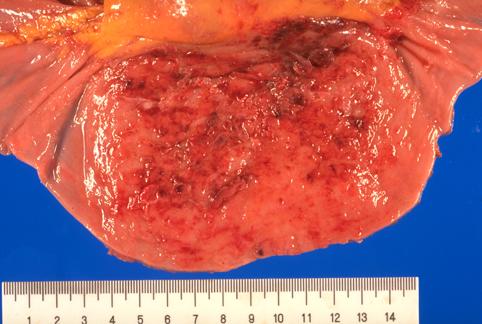

疾患(病理主体)の分類悪性リンパ系腫瘍/悪性リンパ腫

部位(臓器別)小腸/空腸

検査方法マクロ

病変の最大径(ミリ)40以上

腫瘍の深達度s(a)